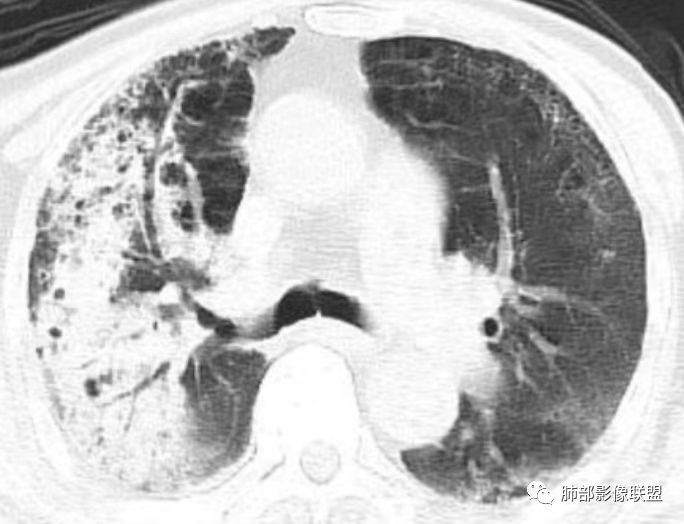

老年男性,糖尿病患者,右肺上叶大片状影伴多发小空洞和支气管充气征,有重力分布趋向,播散灶不明显,两肺胸膜下多发慢性炎症改变,有肺气肿肺大疱背景,肺门纵膈多发小淋巴结,少许钙化,急性起病,首先考虑感染性病变,1.气肿性肺炎?2.肺克?建议结合临床相关实验室检查,影像学角度常规治疗后复查除外粘液腺癌可能。右肺上叶一空洞内见结节影,考虑合并曲菌感染,干酪性肺炎可以,主要没有播散灶,结核待排吧

双肺多发GG0,外周分布,略受重力影响,部分可见囊,右上贴壁实变、气柱征、无璧空洞,卫星灶不明确,有2DM,常规考虑:间质肺基础,合并TB>坏死性肺炎(肺克)>腺癌。非常规:如HIV+,可能存在PCP并TB,似乎有曲菌球

老年男性,糖尿病病史,慢性病程,右胸廓塌陷,右肺沿支气管分布实变及GGO,叶段分布趋势,其内见支气管充气征及虫蚀样空洞,周围间质受累,指向气道来源病变播散,纵隔淋巴结肿大,密度高伴钙化,综合考虑干酪性肺炎。鉴别肺炎型肺癌。

老年男性,有糖尿病史,右肺上叶大片实变影,有支气管充气征,支气管走行僵直,有扩张,有多发无壁小空洞和俩个稍大空洞,胸膜稍增厚,双下肺野间质性改变,考虑肺结核,干酪性肺炎可能性大。

老年男性,右肺上叶大片实变,边界局部清楚,局部模糊,其内见支气管充气征及多发大小不等的小泡状及分枝状无壁空洞。双肺下叶磨玻璃样间质性改变。综合考虑右肺上叶结核,干酪性肺炎可能。

老年男性,咳嗽气喘10天,双肺明显肺气肿,右上肺叶实变,内见大量空洞及囊腔样改变(部分为支气管扩张),实变区周围表现为网格样改变,有明显的小叶间隔增厚,边界似清非清,支气管走行僵硬,有枯树枝样改变,双下肺胸膜下小叶间隔增厚明显,边缘相对模糊,综合考虑如下:1、粘液腺癌可能大(枯树枝样改变,边界似清非清,小叶间隔增厚符合)。2、结核,右上肺似像干酷样改变,内有空洞及支扩样改变支持,但下肺及左肺无相关支气管播散的小叶中心结节及树芽,不支持,临床病症不支持,只有咳嗽,喘气,无咳痰及结核中毒症状。当然结核是妖,需要结合痰检及结核相关指标进一步明确。3、肺克,虽有10年糖尿病史,但肺部只有右肺改变明显,无胸膜下脓肿表现,无脓毒栓表现,临床症状也不支持。4、其他感染?双下肺胸膜下病灶边缘模糊,不完全除外,需要结合临床炎性指标分析。

右上肺大片状高密度影,呈蜂窝样改变,部分气腔无壁,部分呈厚壁改变,内部结构紊乱,部分边缘GGO边界清楚,大小不一,病灶近端小远端大,近端支气管壁增厚,支持感染性病变,考虑结核,其内支气管呈枯树枝改变,病灶局部膨隆,内部结构紊乱,边界的GGO部分清楚,恶性(腺癌)待排。